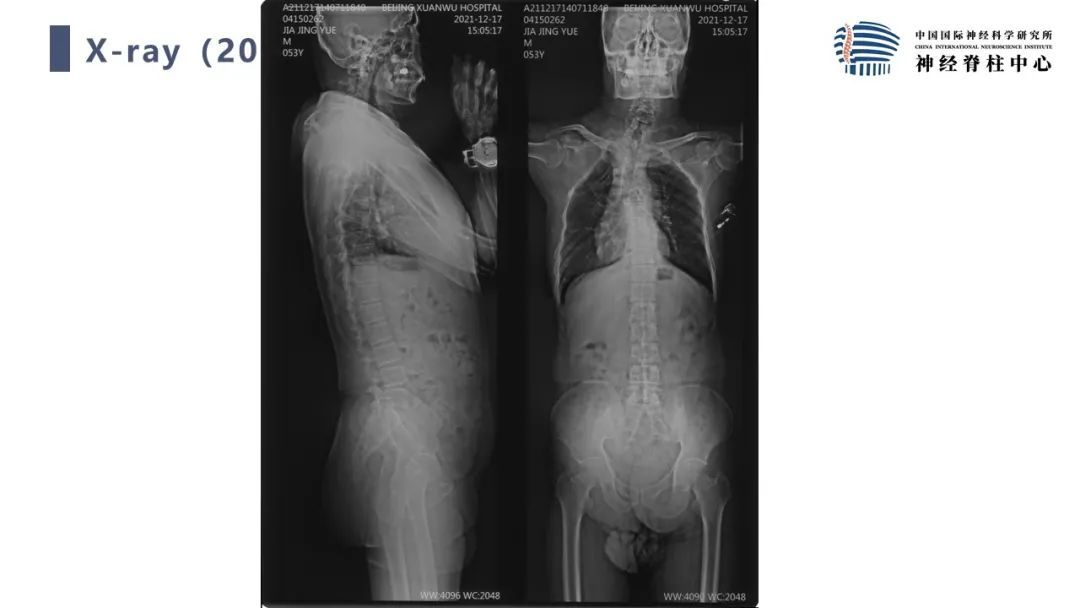

段婉茹副主任医师:脊髓栓系的治疗

首都医科大学宣武医院